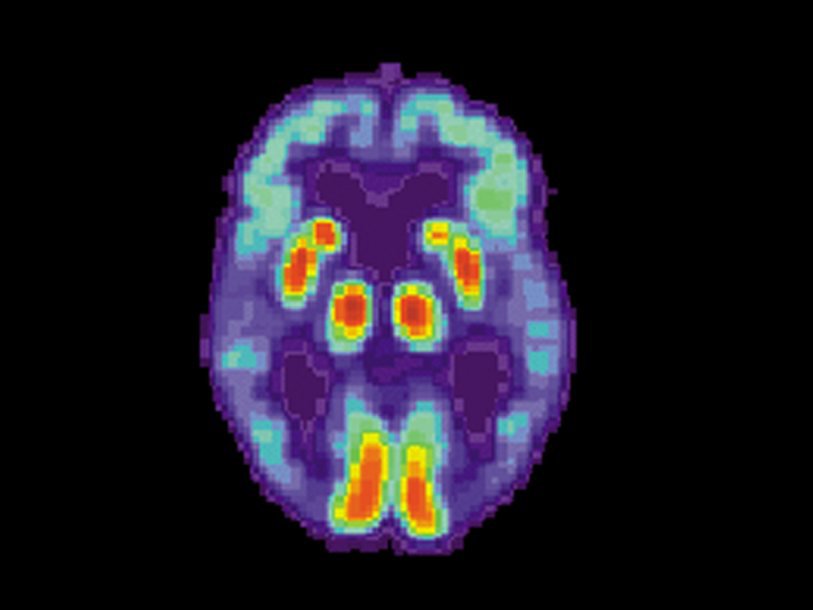

Напомним, что наиболее вероятными причинами болезни Альцгеймера считаются два белка с аномальной структурой, накапливающиеся в тканях мозга: бета-амилоид и тау-белок (подробнее об этом можно прочитать в специальных очерках «Болезнь Альцгеймера: диагностика и лечение» и «Тау-белок и болезнь Альцгеймера», а также в других материалах на эту тему).

Известно несколько пациентов, умерших в Великобритании от болезни Крейтцфельдта-Якоба – типичного прионного заболевания – после лечения зараженным гормоном роста. В период с 1958 по 1985 год этот метод лечения задержки роста у детей был популярен, и такие гормоны получили примерно 30 000 детей. Гормон для этого получали из гипофизов умерших людей, среди которых оказались жертвы болезни Крейтцфельдта-Якоба. Исследователи уже давно обнаружили, что у умерших после получения такого гормона в мозге кроме типичных для этой болезни скоплений белка PrPSc имелись бета-амилоидные бляшки, характерные для болезни Альцгеймера. Но они накапливались не между нервными клетками, как это происходит при болезнь Альцгеймера, а в кровеносных сосудах мозга. Для такого явления даже придумали особый термин – церебральная амилоидная ангиопатия.